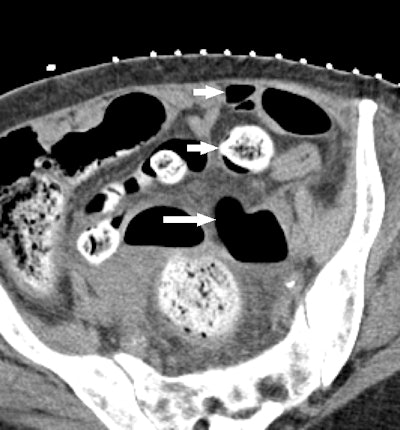

At Brigham, radiologists some time ago modified F-Spoon by cutting a keyhole-shaped notch in the spoon that made it better for guiding needle interventions during CT fluoroscopy studies. By inserting a needle into the keyhole notch, radiologists could compress the abdomen to move bowel loops aside while inserting needles, and they could also keep their hands out of the x-ray beam.

But the proof is in the pudding, so the researchers decided to test their 3D-printed compression paddle by using it in 21 CT fluoroscopy-guided procedures, consisting of 18 biopsies, two abscess drainages, and one liver microwave ablation. They tracked how the device was used and whether the interventional procedure would have been possible without it.

Ultimately, 15 procedures were deemed "questionably feasible" but difficult to perform without the paddle, four were rated as "not feasible" without the device, and two were categorized as feasible without the device but facilitated by the use of it. A particular benefit was the ability to use the paddle to steer the needle by applying pressure against it from inside the keyhole.